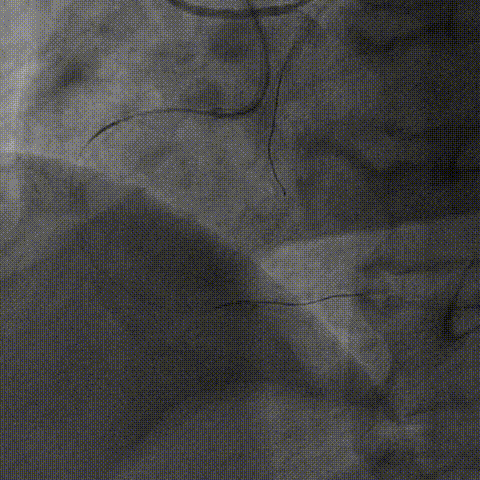

术后IVUS

术后造影

右冠造影,提示右冠近端完全闭塞

于RCA中段选择shockwave 3.5x12mm,8个周期

选择3.5mm后扩球囊,22-24atm扩张

于RCA植入三枚支架:3.0、3.5、4.0